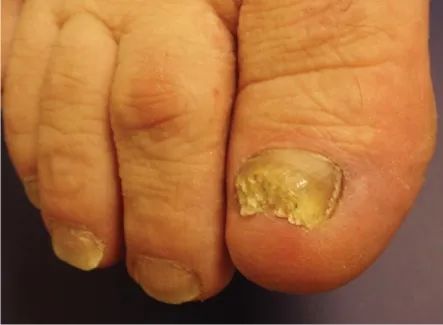

5、指甲增厚

常由甲真菌病引起,除了增厚外,指甲还可有变色、变形等特征。

甲真菌病。图片来源:参考文献[6]